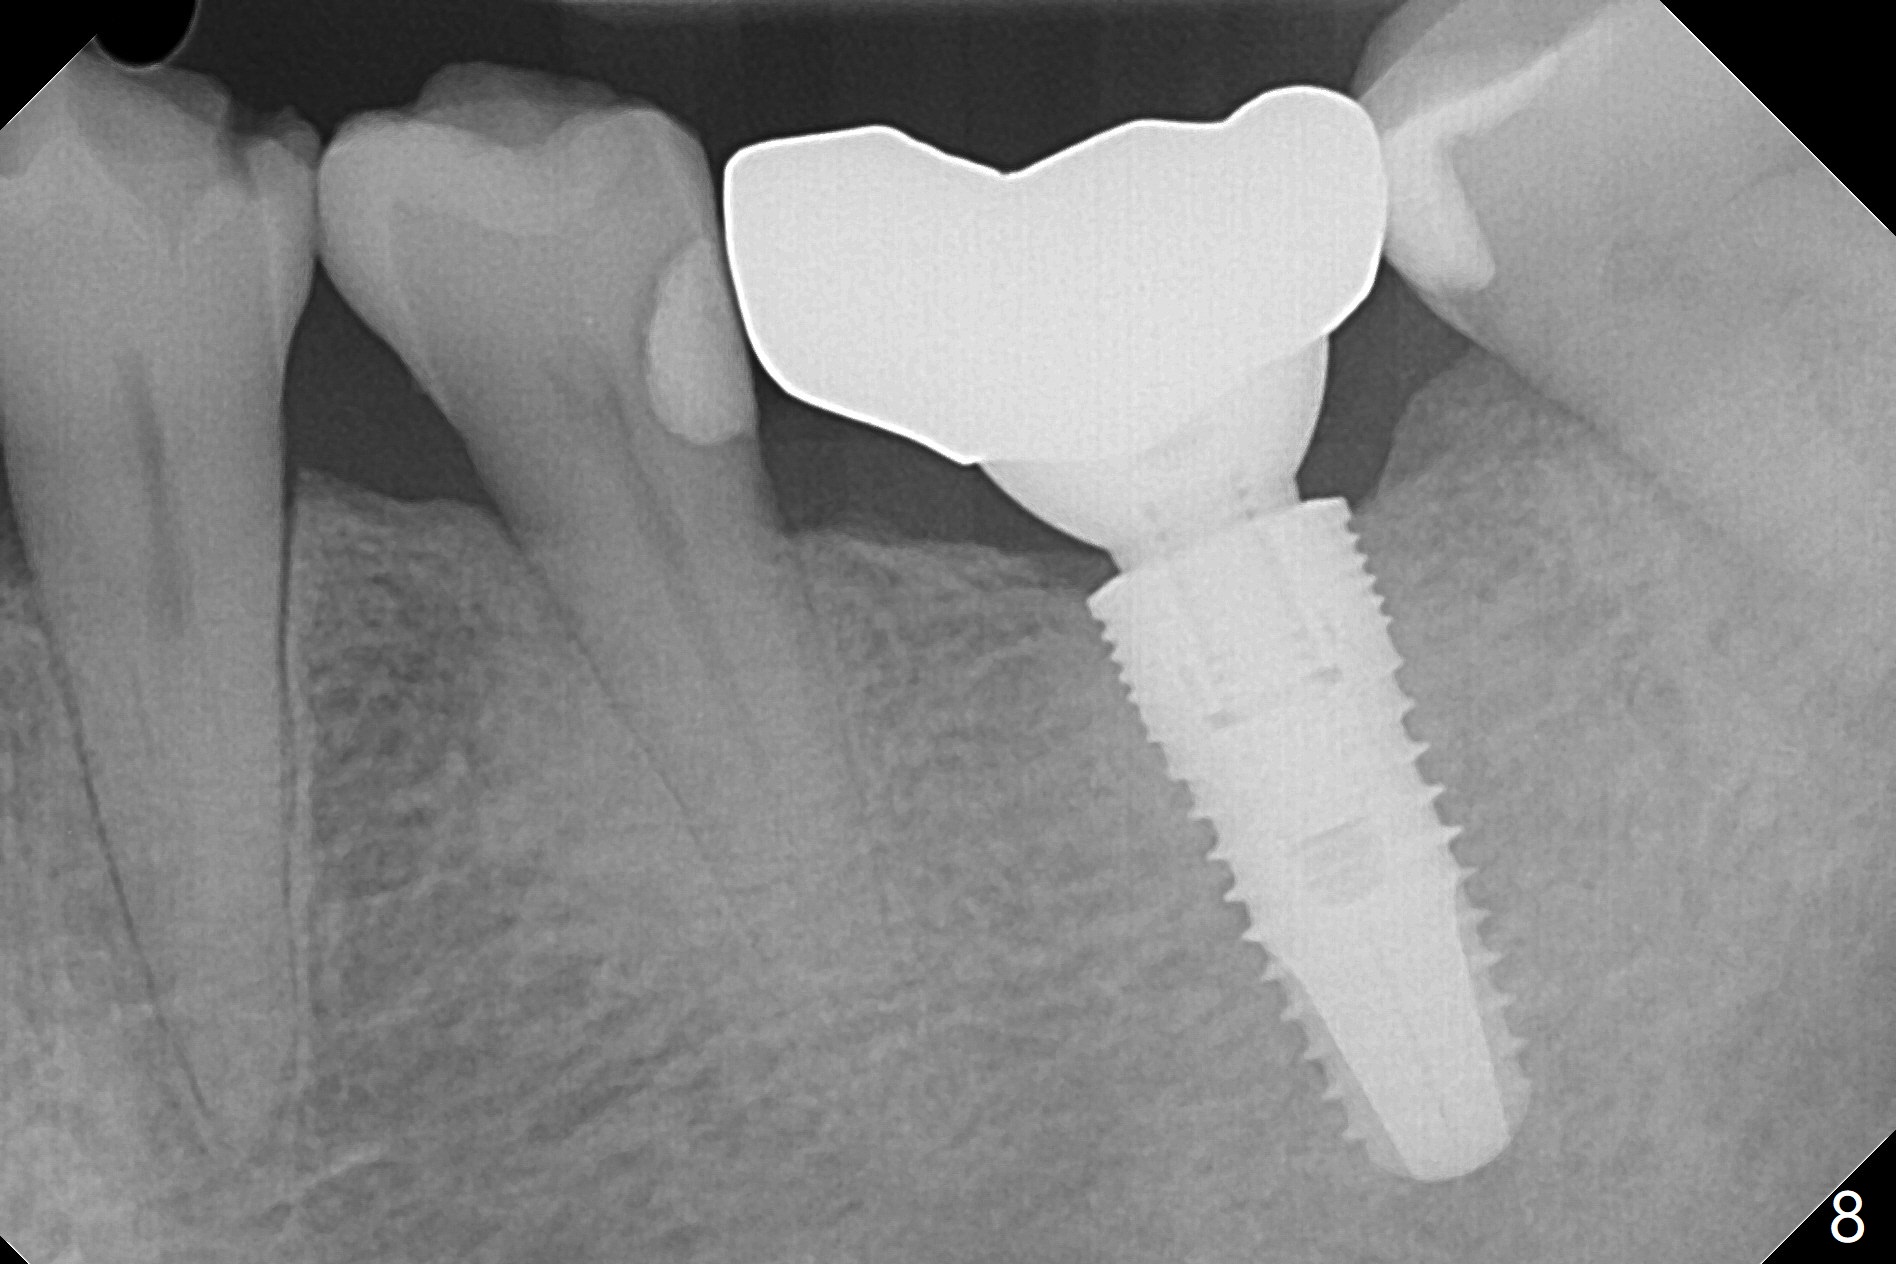

In fact the tooth #14 appears to have been intruded 2 months post-treatment. The composite dislodges 3 months later. A new crown with screw retained is fabricated, but the patient cannot masticate well on the left. DO caries of the tooth #20 is found (Fig.7) and restored (Fig.8). As a matter of the fact, the food impaction is reported between #18 and 19! What can we do now?